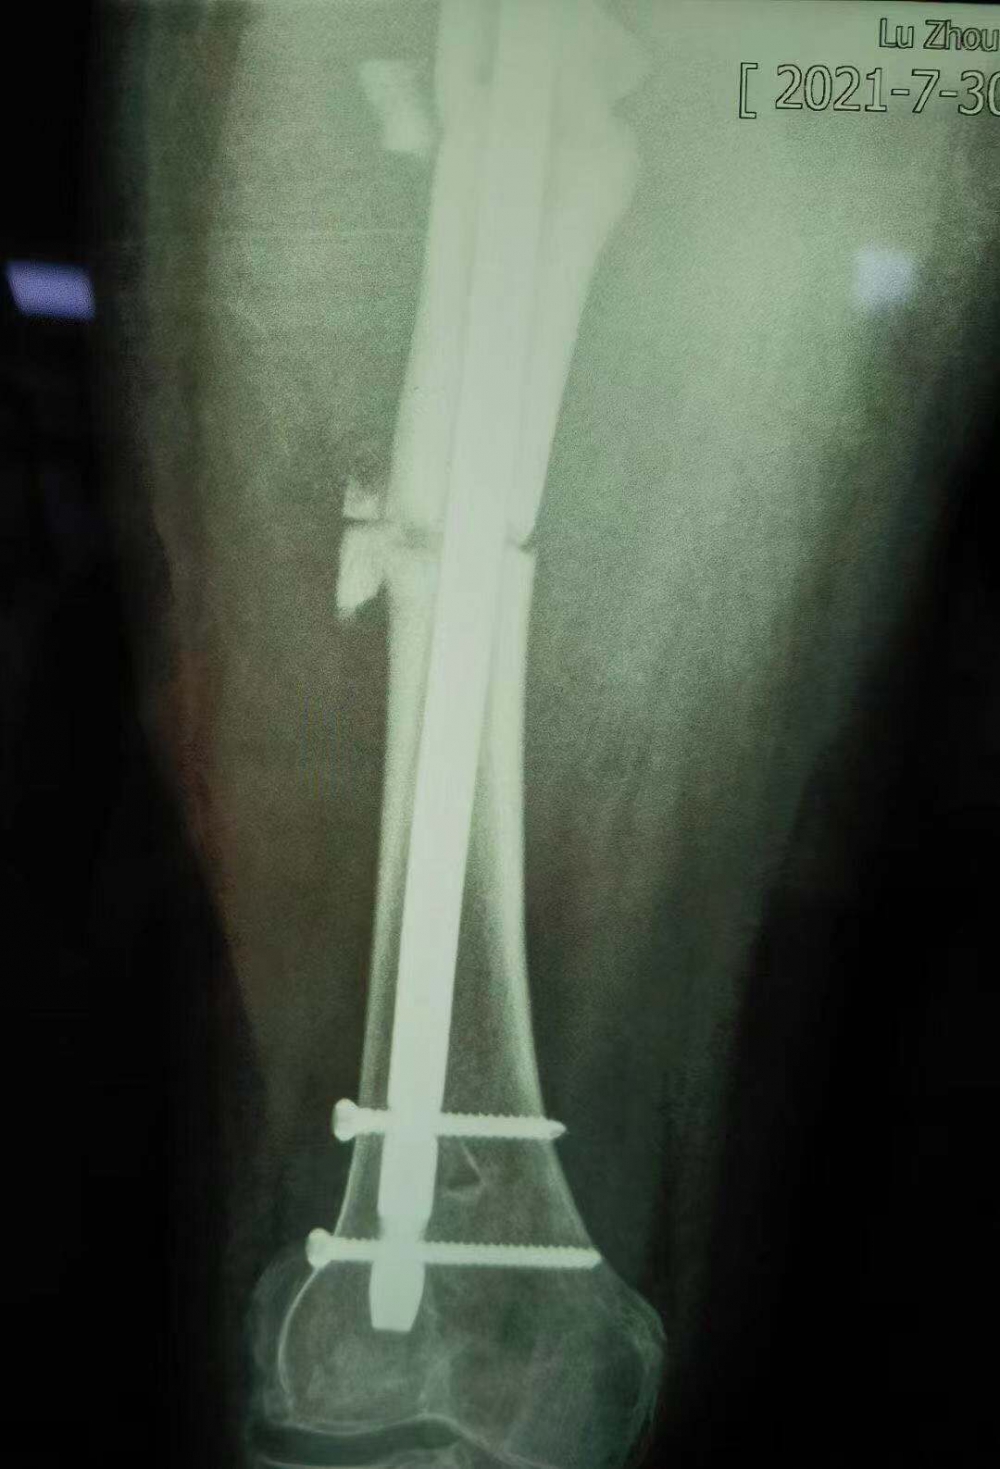

據(jù)汪永泉主任介紹,此次手術(shù)很成功,術(shù)后通過觀察,病人目前沒有血管的危象,而且整個神經(jīng)沒有牽拉,而且病人整個下肢體長度,也基本達到術(shù)前預想的恢復長度。

術(shù)后拍攝的X光片

但因張女士屬于股骨上段骨折畸形以后手術(shù)歸正,整個股骨頭的負重區(qū)已經(jīng)發(fā)生了一些改變,髖關(guān)節(jié)關(guān)節(jié)炎也可能存在,因此張女士還需進行后續(xù)的康復性治療和護理。